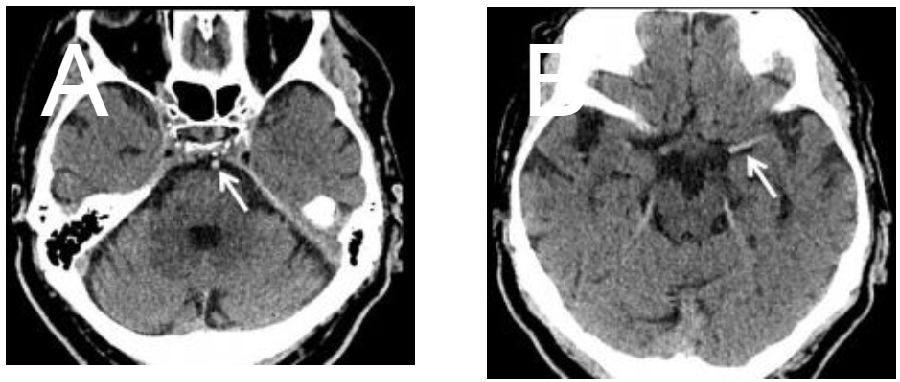

头颅CT平扫

显示基底动脉(A)和左侧大脑中动脉(B;箭头)有高密度血管征。